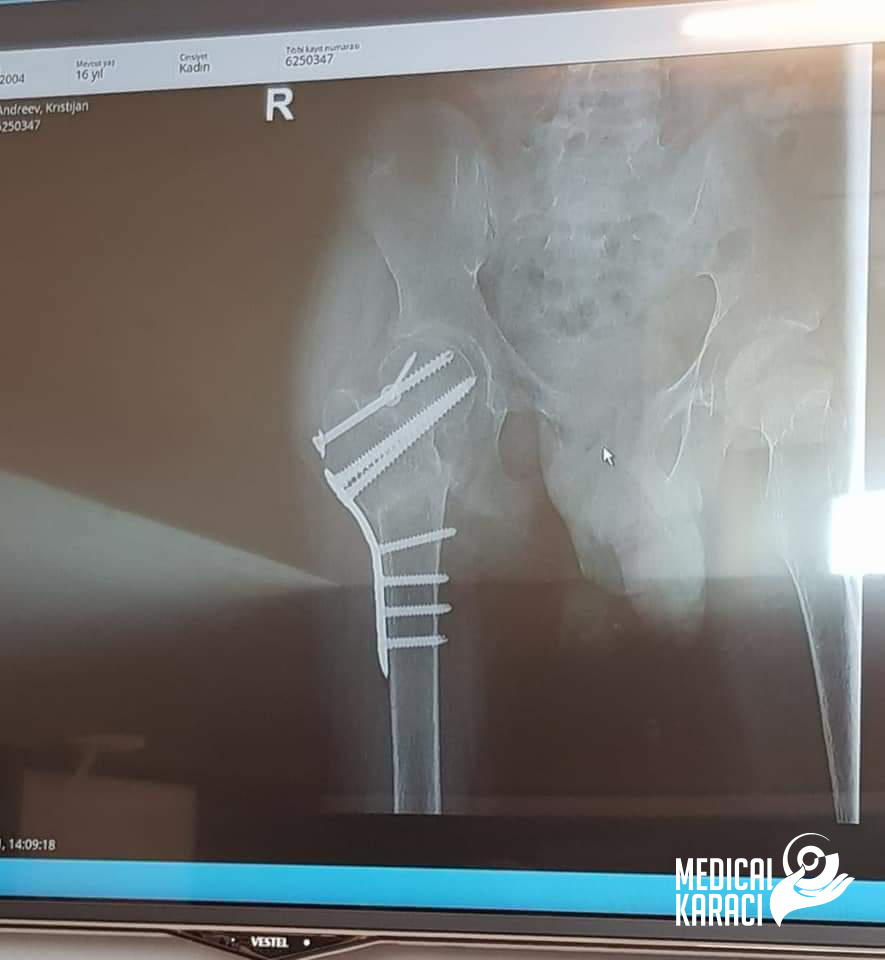

Kristijan 17 yaşında çok ağır bir otizm ve epilepsi hastası bir çocuktur, Aralık 2020'de düşmüş ve vurulmuştur. Makedonya'daki Koga sitesi kazuvaa ni deka nemoze da ho ho operiraat i deka nema nikogash veke da zastane na noge i da odi jas ne se otkazav, no nitu ti mila moja Zvezdelina Kara i Karaci Tours Medical denonokno istrazuvashe, him barashe i him najdobroto za Kristijan !Kristijan blagodarenie na te te i na Prof. Dr. Mustafa Kürklü ZASTANA NA NOZE I ODI 🙏🙏Neznam kako da ti se zablagodaram za se shto napravi i pravish za Kristijan, za celata organizacija vo bolnicata Memorial Bahçelievler Hastanesi Bizimle olduğun her zaman için. Bu yüzden bizimle birlikte seviniyor ve savaşıyorsunuz🙏